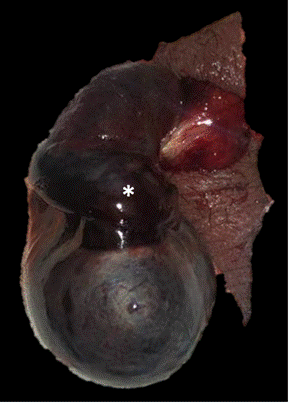

Expone testículo derecho cianótico con cambios hemorrágicos en el cordón espermático a través del sitio de incisión escrotal (*). Origen: Servicio de Diagnóstico por Imágenes. Hospital Italiano de Buenos Aires. Buenos Aires, Argentina. 2021.

Figura 3a Anatomía patológica